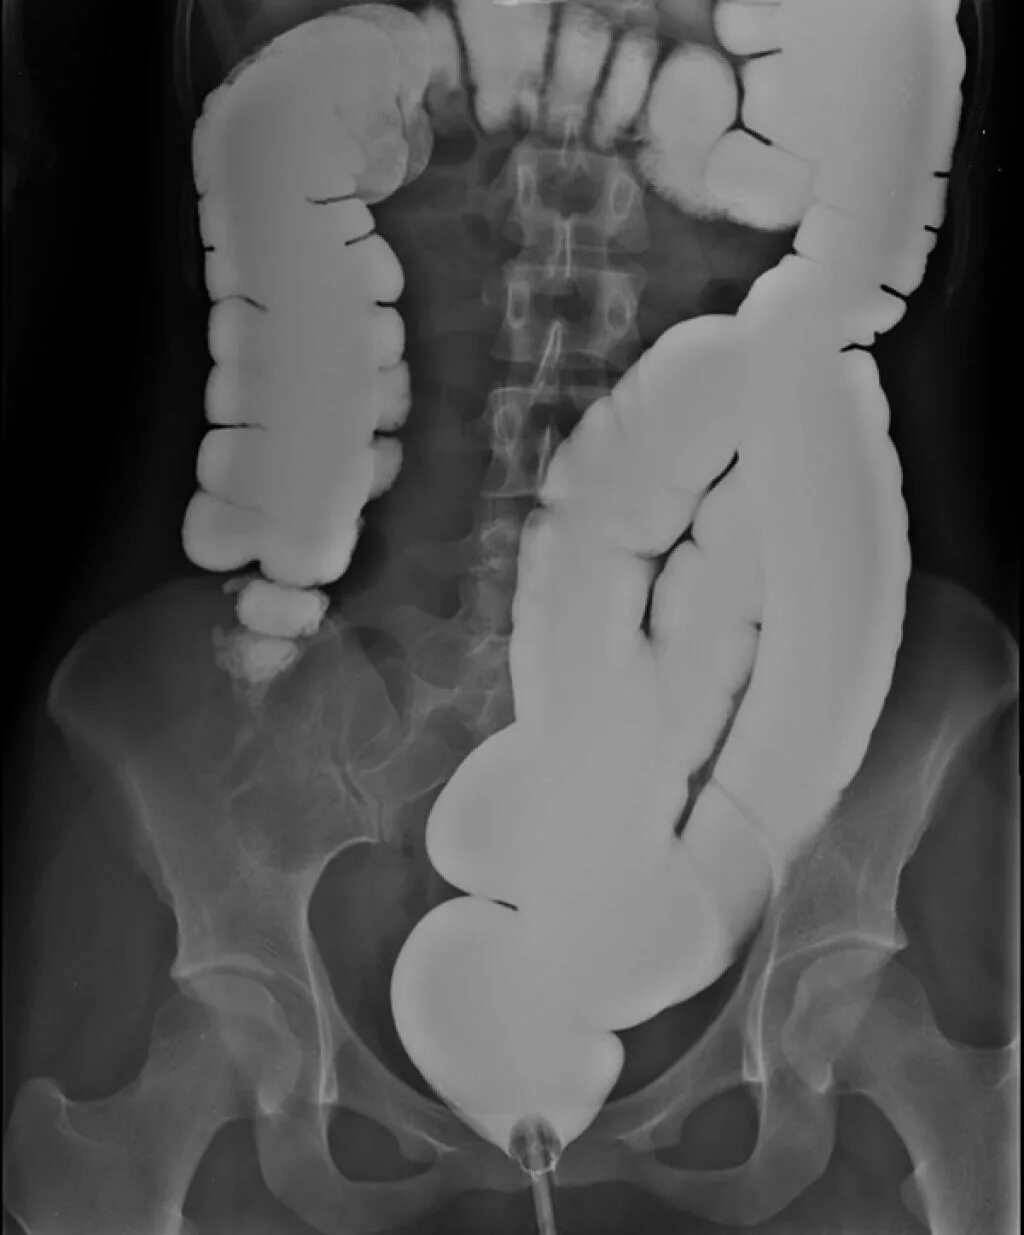

Ирригоскопия как проводится видео